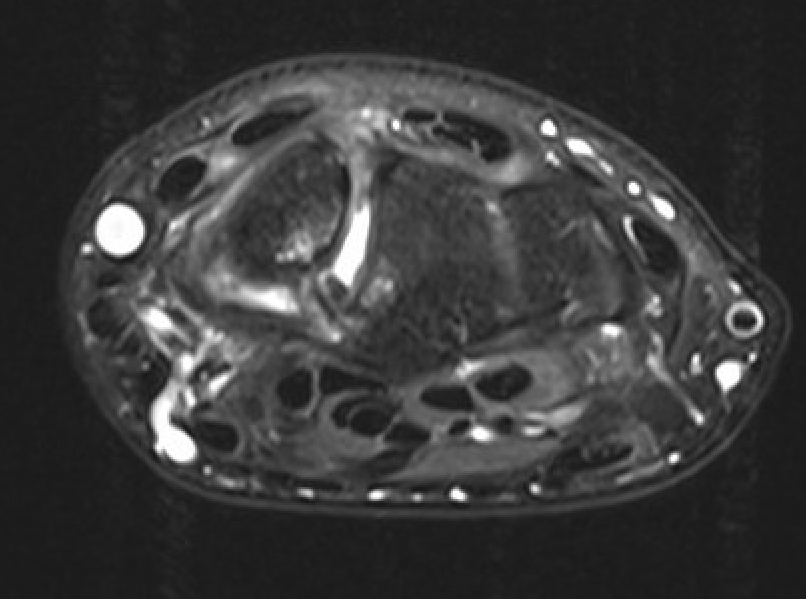

MRI

SL ligament injury with minimal disassociation / SL separation / dynamic instability

SL ligament injury with SL separation and static instability

Increased scapholunate angle